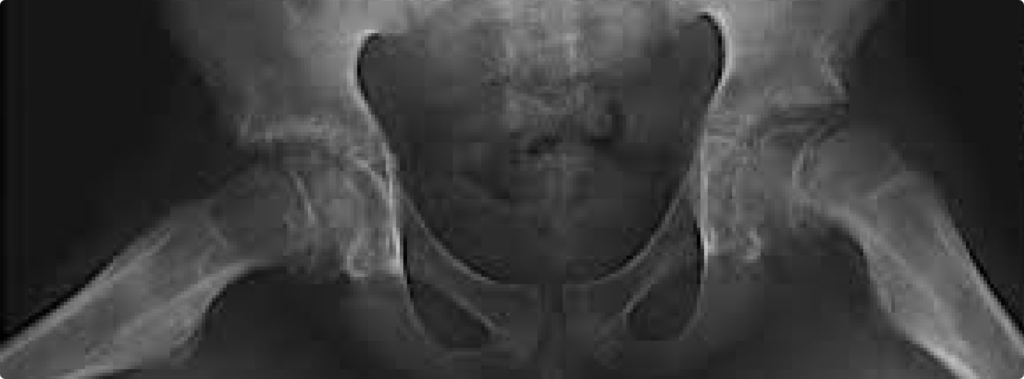

Displasia do Desenvolvimento do Quadril (DDQ)